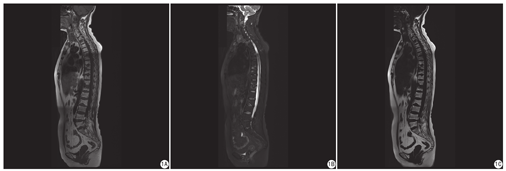

22例患者均于2018年3~4月于首都医科大学附属北京中医医院放射科应用全脊柱标准化扫描方案进行MRI检查。本研究获得首都医科大学附属北京中医医院伦理委员会批准(伦理文件编号:2018BL-0-050-01)。所有患者均已签署知情同意书。应用西门子Magnetom Skyra 3.0 T超导磁共振仪对临床确诊的SAPHO综合征患者全脊柱线圈进行基线扫描,使用自动移床跟踪扫描技术将全脊柱分为颈部、胸部及腰部三段扫描,最后应用Composing全脊柱成像软件进行拼接,具体参数为:全脊柱扫描序列为矢状位T2WI DIXON序列,颈椎:TR 3000 ms,TE 110 ms,层厚4 mm,FOV 260 mm×260 mm;胸椎:TR 3080 ms,TE 112 ms,层厚3 mm,FOV 330 mm×330 mm;腰椎:TR 3140 ms,TE 112 ms,层厚4 mm,FOV 240 mm×240 mm。矢状位T1WI,颈椎:TR 600 ms,TE 9 ms,层厚3 mm,FOV 260 mm×260 mm;胸椎:TR 600 ms,TE 8.7 ms,层厚3 mm,FOV 320 mm×320 mm;腰椎:TR 650 ms,TE 9.5 ms,层厚4 mm,FOV 320 mm×320 mm。

综上,本研究通过对临床确诊的22例SAPHO综合征患者进行全脊柱MRI评估,特征性病变BME和脂质沉积,主要累及胸段前椎角,以跳跃性和对吻性分布为主。以上特征有助于临床及影像科医生更好地理解本病,避免误诊。

SAPHO综合征全脊柱病变以胸椎前侧椎角的BME和脂质沉积为主,呈跳跃和对吻分布,具有一定的特征性。

MRI可明确显示脊柱的活动性病变,如BME[12],也可以发现一些无症状的病变[5],为临床治疗提供依据[13]。本研究中所有患者均为多节段病变,45.4%累及胸椎,其次为腰椎、颈椎,有2.9%的椎体病变累及椎弓根,多数表现为脂质沉积,这与既往文献报道病变多累及胸椎一致[5],与有的研究结果显示病变主要累及腰椎或颈椎不一致[4,14,15,16]。在病变分布方面,63.0%的BME、63.4%的脂质沉积位于椎体前部,且为多发病变,这与既往研究指出的病变多位于终板的前部或中心部略有差异[5]。另外,本研究发现46.7%的BME、58.7%的脂质沉积呈对吻分布,这个比例远高于与Laredo等[17]报道的12%的椎体病变呈连续性分布,而又低于徐文睿[8]所报道的80.3%,可能与报道病例数以及病变的不同时期有关。既往X线研究报道SAPHO综合征椎体病变多从1个椎角开始,由骨髓炎症逐渐转变为椎角骨皮质的损害,MRI多表现为伴有BME的骨皮质缺损[18,19];后期X线和CT示骨质硬化形成"闪亮"的高密度征。BME作为活动性病变的代表征象,本研究中仅占28.9%,而脂质沉积所占比例最高,17.0%的病变椎体上同时存在BME与脂质沉积,多数分布在椎角,呈现"BME包绕脂质沉积"的形式。Leone等[14]认为脂质沉积是脊柱非特异性炎症的表现之一,也有研究指出脂质沉积在脊柱关节炎的骶髂关节病变中起到重要的作用[20],脂质沉积在SAPHO综合征中的作用是否也是BME的填充,有待于进一步研究。